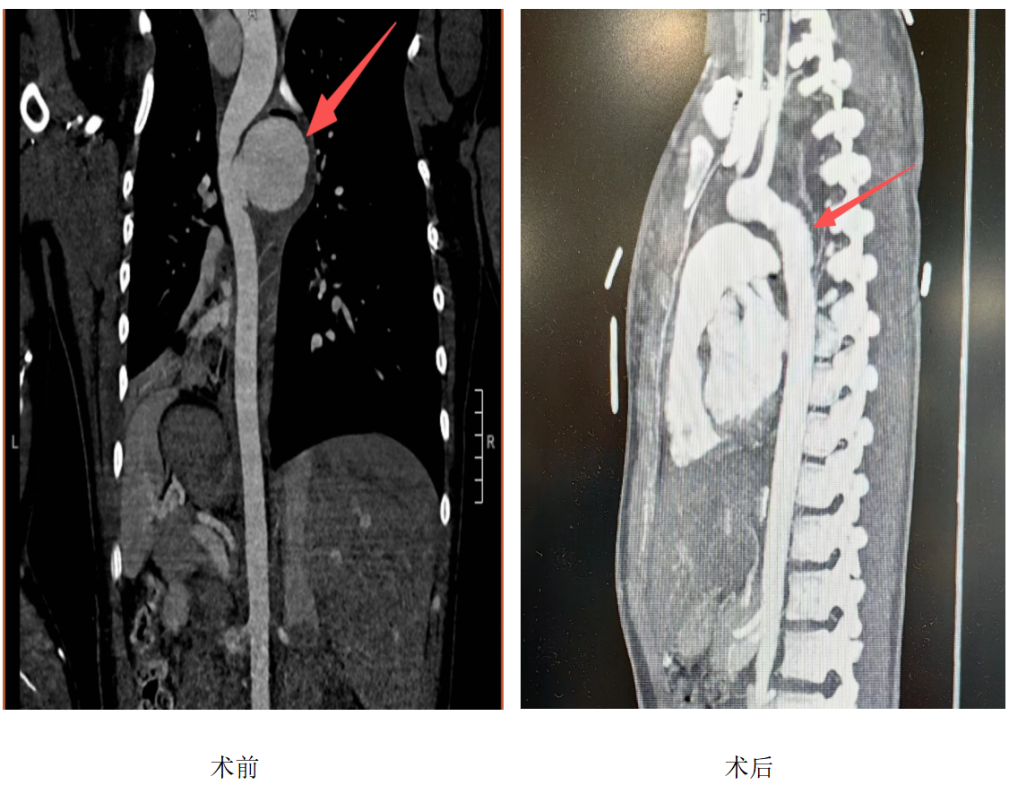

与12岁的梦梦(化名)一起送到医院的还有密密麻麻的诊断书:骨盆、胫骨、胸骨、肋骨及腰椎骨折,双肺挫伤,脾脏破裂伴腹腔积血,蛛网膜下腔出血,闭合性颅脑损伤及急性创伤性主动脉假性动脉瘤等全身多处损伤。

主动脉假性动脉瘤是指创伤等因素导致主动脉壁破裂出血被邻近组织包裹,形成与主动脉腔相通的搏动性肿块,一般瘤口小,瘤体大,瘤壁为机化的血栓和与周围脏器粘连包绕的纤维组织,而不是正常的动脉壁结构,故容易破裂造成致命性大出血。

时间一分一秒流逝,在罗洪波沉稳的操作下主动脉瘤被精确地分离,病变血管及瘤体精准切除,人工血管成功置换,胸腔“炸弹”顺利拆除。

主动脉假性动脉瘤大多继发于主动脉损伤,如外伤、刀刺伤、手术创伤。主动脉位于人体的正中央,周围有胸廓及纤维组织的保护,当暴力等因素导致主动脉破裂或急性假性动脉瘤形成时,85%以上的患者当场死亡,仅2%~5%的主动脉钝性损伤可以发展为慢性假性动脉瘤 。故主动脉假性动脉瘤患者在主动脉扩张性病变中所占的比例虽小,但病情更为凶险,一经诊断,应尽早手术治疗。